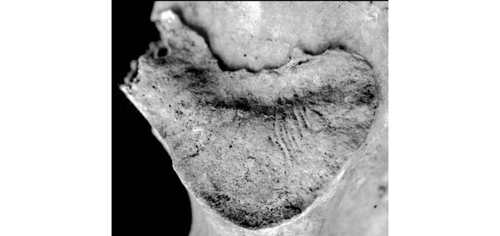

SSPIA (Organisation Transverse)

Ondulations ou stries organisées perpendiculairement par rapport à l’axe du segment vertical et horizontal de la surface articulaire. Les ondulations sont de légères crêtes séparées par des sillons (« rides »). Les stries sont une forme très atténuée des ondulations.